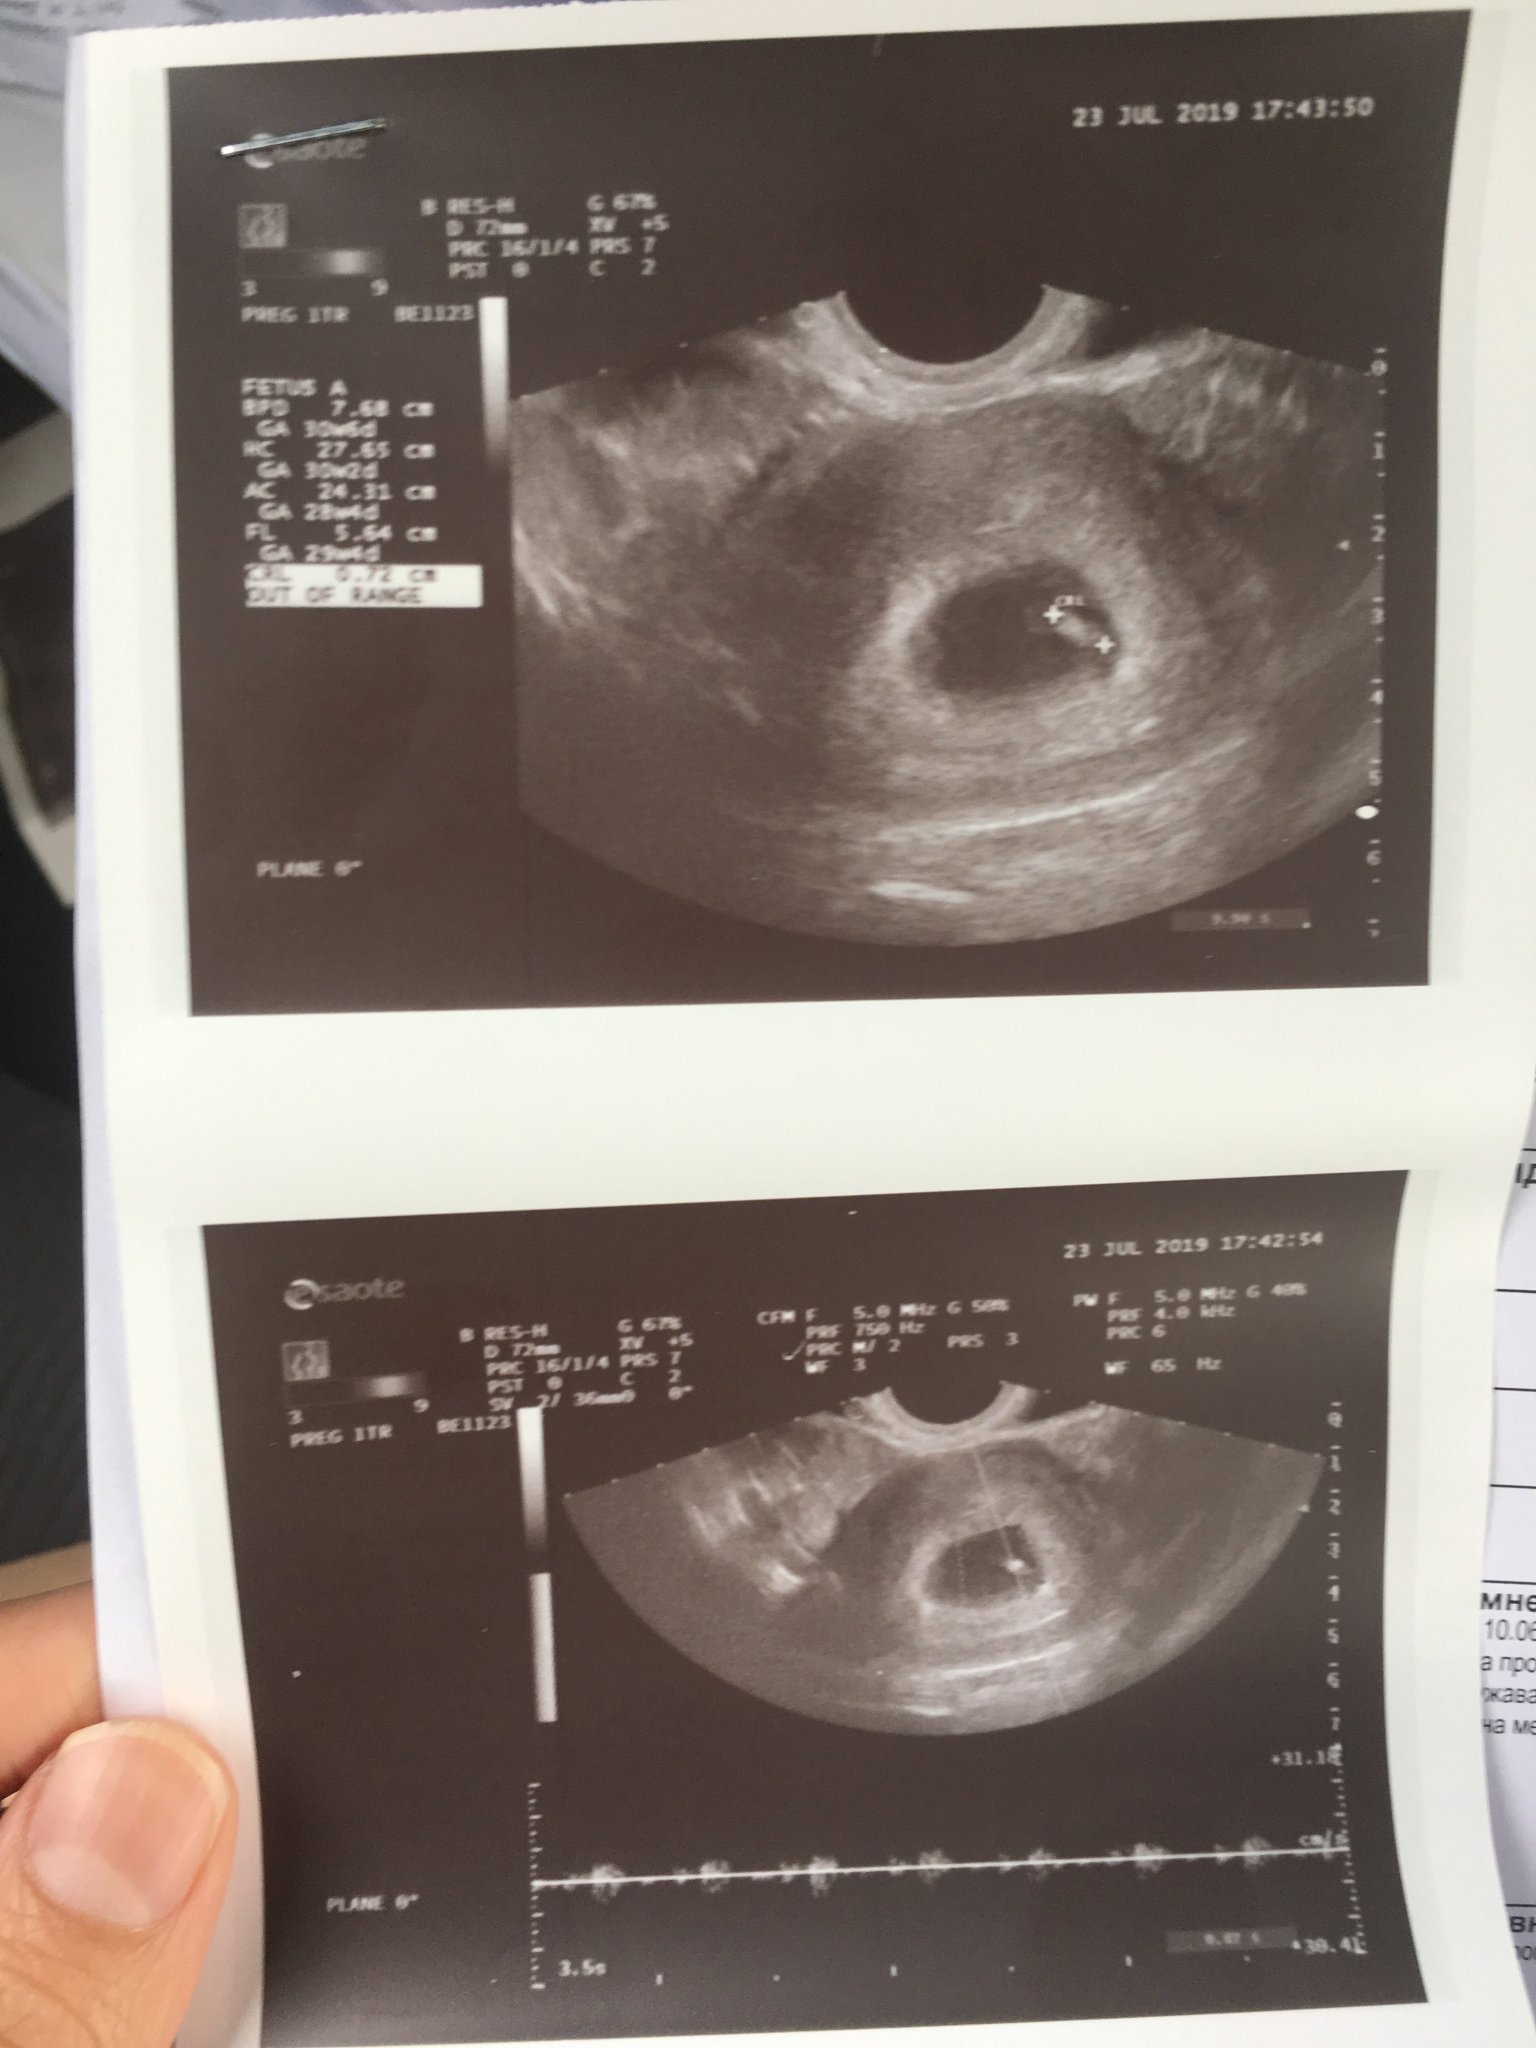

Хайде да Ви се похваля😀 Страхотен подарък за утрешния ми рожден ден. Поръсваме ви всички с този късмет!6сед.+1 ден видяхме ембрионче 7мм и чухме сърчице. Моля се всичко да е наред и занапред, че тази една седмица се измъчих докато дойде прегледа, заради страха от “кухо яйце”..